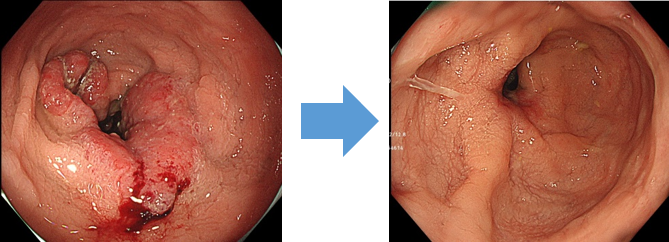

難易度の高い病変や良性病変にも対応

大きな病変や傷あとがある部位、再発などの難易度の高い病変にも対応しております。全身状態や高齢などの理由により手術を回避したい早期がんの方も、症例によっては内視鏡切除による対応が可能です。

症例によっては、早期がんではあるが内視鏡単独治療が困難な場合など、内科と外科共同で腹腔鏡と組み合わせたハイブリッドESDも行っております。